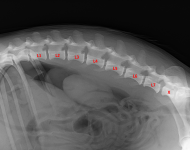

MVDr. Meloun: Lumbosakrální přechodový obratel